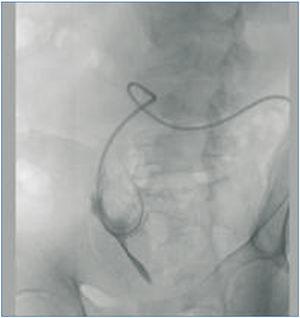

Caso 3. Paciente de 72 años, que tras 15 meses en APD empieza a presentar problemas para el drenaje a pesar de utilizar laxantes. Se comprueba que la punta está en epigastrio y se recoloca mediante guía (figura 3).

Figura 3. Caso 3